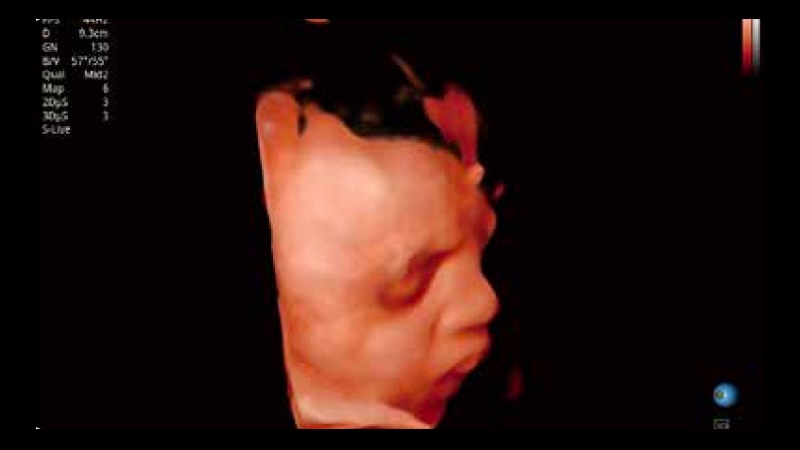

開立醫(yī)療通過不斷的技術(shù)創(chuàng)新,為大眾的生命健康提供持續(xù)關(guān)愛。P12 Plus采用全新一代超聲成像平臺(tái),新平臺(tái)旨在將真實(shí)還原組織解剖結(jié)構(gòu)作為首要目標(biāo)。平臺(tái)采用全新集成化硬件模塊,搭載新一代芯片,系統(tǒng)性能得到大幅提升,為您的診斷提供了豐富的臨床信息。優(yōu)異的圖像表現(xiàn),豐富的探頭配置,全面的應(yīng)用功能,為您日常診斷提供了可靠的助手。

彩色多普勒超聲診斷系統(tǒng)